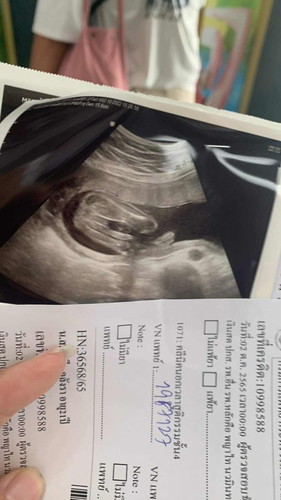

วันนี้ไปหาหมอ ดูเพศลูกมา เเต่ตอนหมอ อัลตราซาวด์เเล้ว สายสะดือไปพันตรงขาน้องพอดี เลยดูไม่ชัด อยากไห้เเม่ๆช่วยดูเพศหน่อยค่ะ

หน้าจะผู้หญิงค่ะ บ้านนี้ผู้ชายโผล่มาทั้งยวงเลยค่ะ 🤣🤣

น่าจะเป็นหญิงนะคะแม่

น่าจะผู้หญิงนะคะ

น่าจะผู้หญิงค่ะแม่

เราว่าผู้หญิงคะ

เดาว่าหญิงค่ะ

หมอเขาบอก ผู้ชาย 80% เลยยังไม่กล้าซื้อของเลยค่ะ